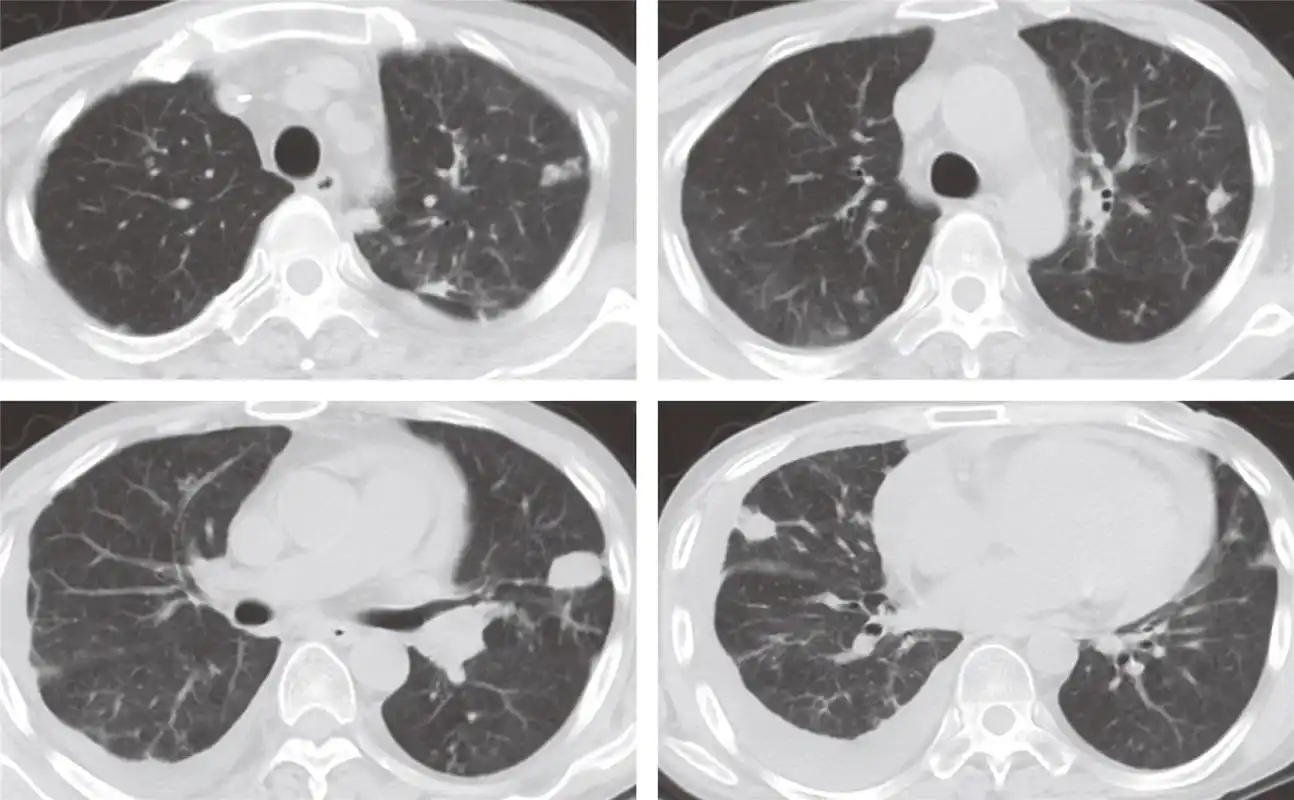

双肺支气管肺炎-ct图

双肺下叶多发树芽征,小叶中心结节灶麻疹病毒肺炎:双肺多发沿支气管

在ct上表现有:又称为小叶性肺炎,多见于婴幼儿,老年人及免疫功能损害